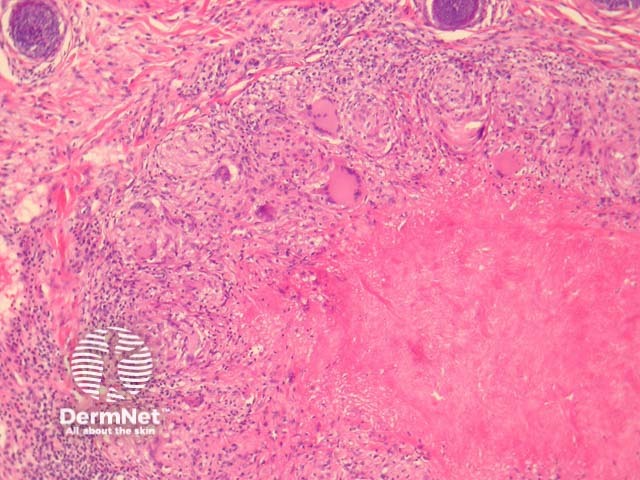

In LMDF, sections show round granulomas with central caseating necrosis. The granulomas may appear sarcoidal or tuberculoid. The granulomas typically arise adjacent to adnexal structures. A chronic infiltrate often accompanies the granulomas. See figures 1-4.

Figure 1